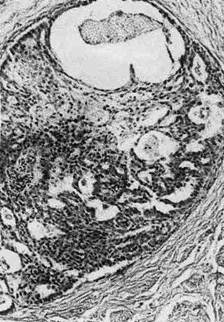

1. «Рак на месте», или carcinoma in situ (интраэпителиальная,

Рис. 138. Рак на месте

с атипичными митозами (рис. 138). Рост опухоли происходит в пределах эпи-

телиального пласта, без перехода в подлежащую ткань. Эта форма рака опи-

сана и подробно изучена в шейке матки, описана в слизистой оболочке горта-

ни, желудка. Неинвазивный рак — этап роста опухоли. Со временем он

становится инфильтрирующим (инвазивным).